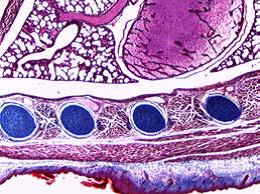

观察微小细节

光学品质**,呈现*精细的样本细节